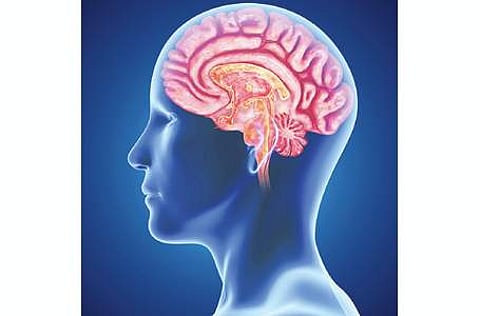

மூளையை புத்துணர்ச்சியுடன் வேலை செய்ய வைக்கும் உணவுபொருள்கள் நிச்சயம் உங்கள் உணவில் இருக்க வேண்டியது அவசியம். இது வெகுநாள் செயல்பாடுகளுக்கு மிகவும் அத்தியாவசியமாக அமையும்.

மூளைக்கு ஊக்கமளிக்கும் உணவுகளை சாப்பிடும்போது மூளையின் செயல்திறனில் நல்ல மாற்றம் தெரியும். மூளையின் செயல்திறனை அதிகரிப்பதோடு, மிகச் சிறப்பான செயல்பாடுகள் மூலமாகவும் அதனை உணர முடியும்.

எப்படி நமது உடலுக்குத் தேவையான ஆரோக்கியமான உணவுகளை நாம் சாப்பிடுகிறோமோ அதுபோல மூளையின் செயல்திறனை ஊக்கப்படுத்தும் உணவுகளையும் தேர்வு செய்து சாப்பிட வேண்டியது கட்டாயமும் கூட.